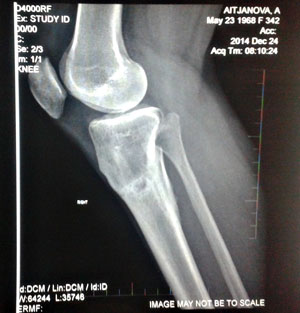

Здравствуйте, Алмагуль! Спасибо за поздравления! Очень рады за Вас, ножки супер, мы гордимся своей работой - таким результатом! Нагрузка Вам разрешена без ограничений, рентген отличный! Всё у Вас железно, не переживайте, живите полной жизнью, на зависть всем!Здравствуйте, Николай Николаевич и Наталья!

Чувствую себя хорошо, ноги не беспокоят, после снятия аппарата еще два месяца носила бандаж для страховки, обувь ношу только на низком.

24-того декабря делала рентген,если есть необходимость, то я вышлю его по почте на следующей неделе.

Хотела бы узнать Ваши комментарии по поводу рентгена. Еще хотела бы узнать можно ли увеличить физ. нагрузки,носить каблуки?